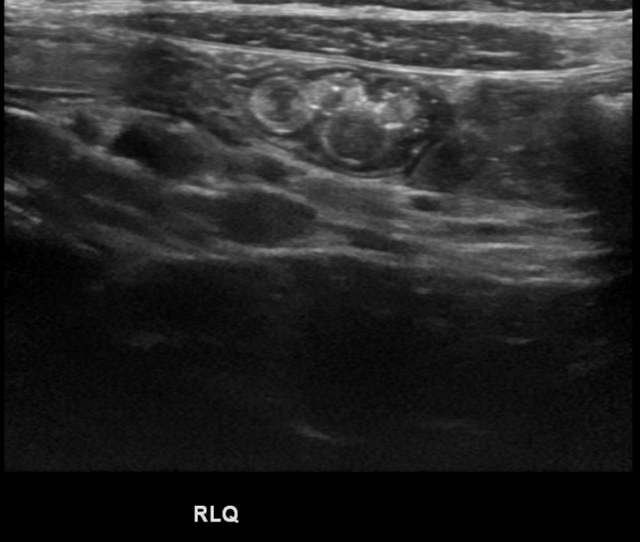

Ascariasis: Image 2

Wayne Fu, MD, Josh Greenstein, MD, Amit Ramjit, MD

Transverse abdominal image showing a loop of bowel containing multiple smaller diameter circular structures with isoechoic wall and hypoechoic lumen. These structures represent intraluminal parasites in cross section.